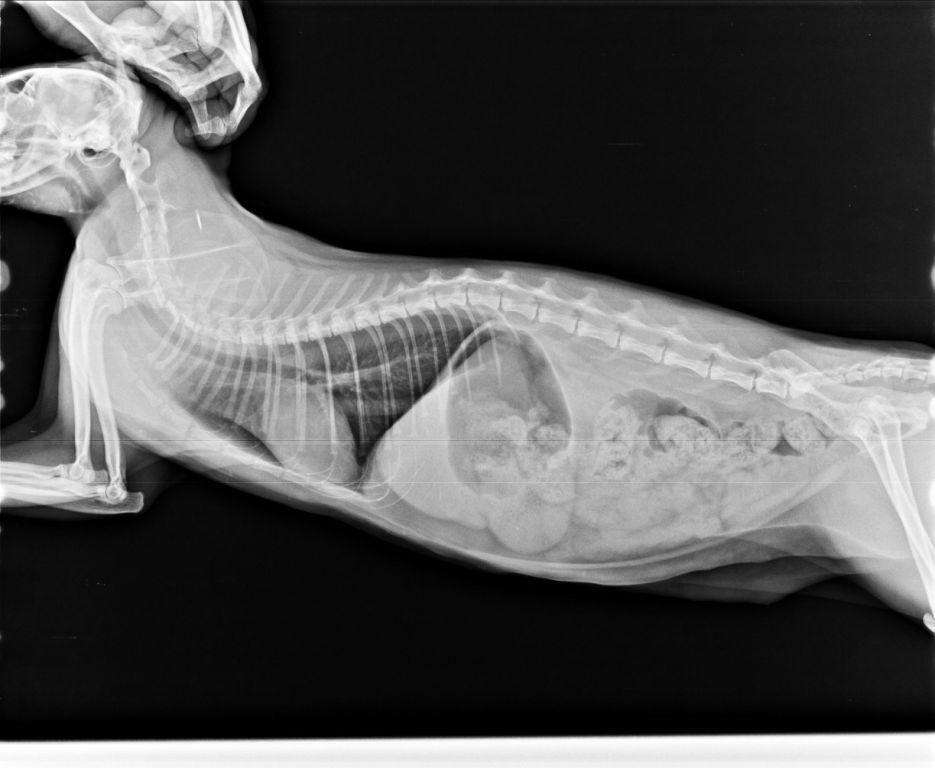

白親親於住院期間由於嚴重的口水不止以及鼻塞導致張口呼吸

不吃不喝因此院方替白親親裝設食道胃管

治療後逐漸穩定而出院